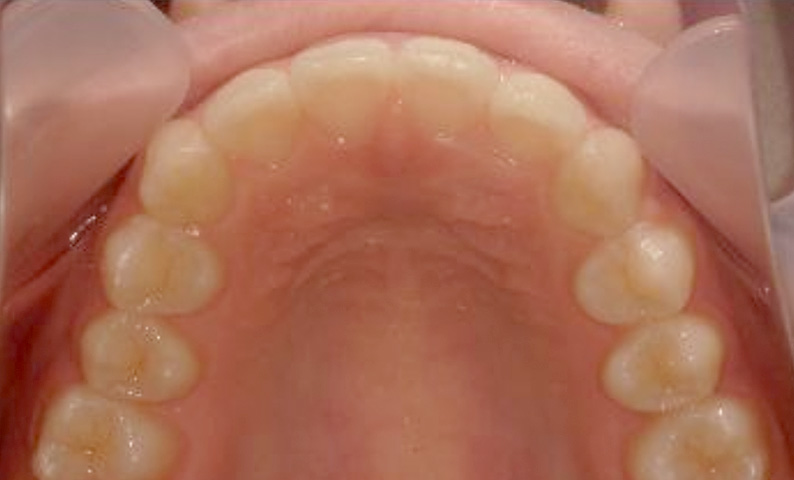

症例_001 上顎だけの部分矯正

治療期間:7ヶ月金額:30万円+税女性出っ歯上の前歯だけ

| Before | After |